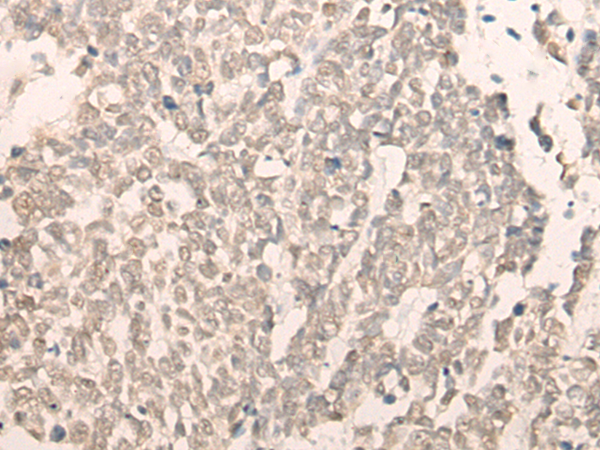

The image is immunohistochemistry of paraffin-embedded Human lung cancer tissue using (RBM17 Antibody) at dilution 1/40. (Original magnification: ×200)